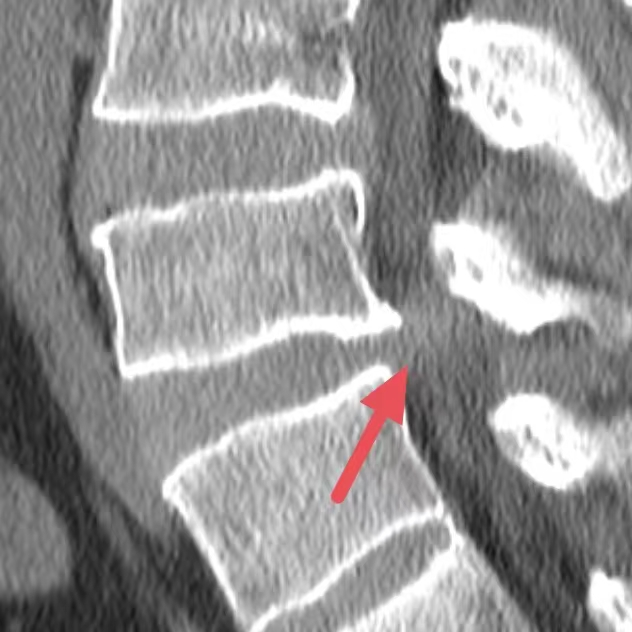

(CT发现胸10骨折,磁共振发现胸9、12损伤)

(腰2骨折伴相应水平椎管内肿瘤MR及显微镜下所见)

魏某,男,48岁,“上楼梯时不慎摔伤”致腰部疼痛、活动受限入院,MR(磁共振)检查显示:L2椎体骨折,腰2水平椎管内占位性病变。经外三科(神经外科、脊椎外科)主任、副主任医师吴隆俊团队讨论并经家属同意后一期行:显微镜下椎管内病损切除术 腰椎骨折内固定术。术后恢复良好,避免患者多次手术。